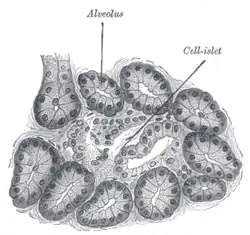

Illustration of dog pancreas. 250x.

Illustration of dog pancreas. 250x.